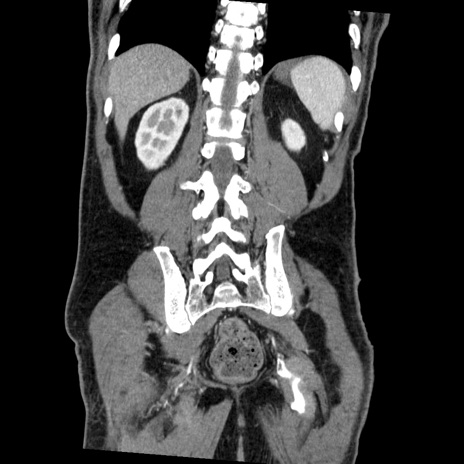

症例22(冠状断像)

【症例】50歳代男性

【主訴】腹痛

【現病歴】AVMからの被殻出血のため回復期リハ病棟入院中。 本日午後3時頃急に下腹部痛が出現した。

【既往歴】AVM、被殻出血、虫垂炎、高血圧

【身体所見】意識晴明、左半身不全麻痺、会話の理解は良好、36.5°C、腹部:膨隆、全体に板状硬、下腹部正中に圧痛点あり、反跳痛-、筋性防御不明、右下腹部にope scar

【データ】WBC 9400、CRP 0.06

横断像